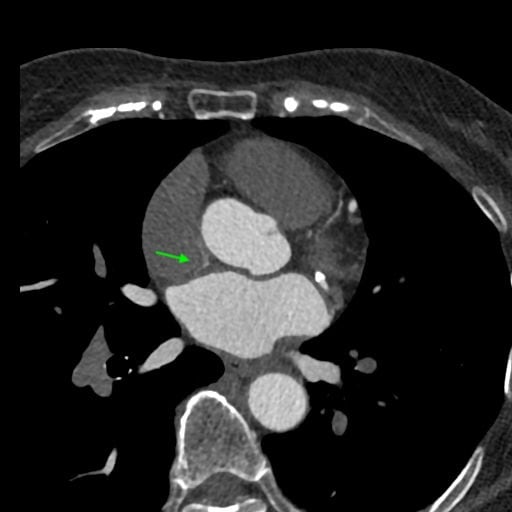

図5.左房から細い血管構造

右上肺静脈の左房開口部腹側から細い血管構造が起始。左房中隔を下降

図6.左房内への造影剤ジェット疑い

造影剤ジェット。左心系は造影され、右心系は造影されてないタイミングで撮影されているため見られる所見。希釈TI法によってタイミング、造影効果が適切に管理されている。